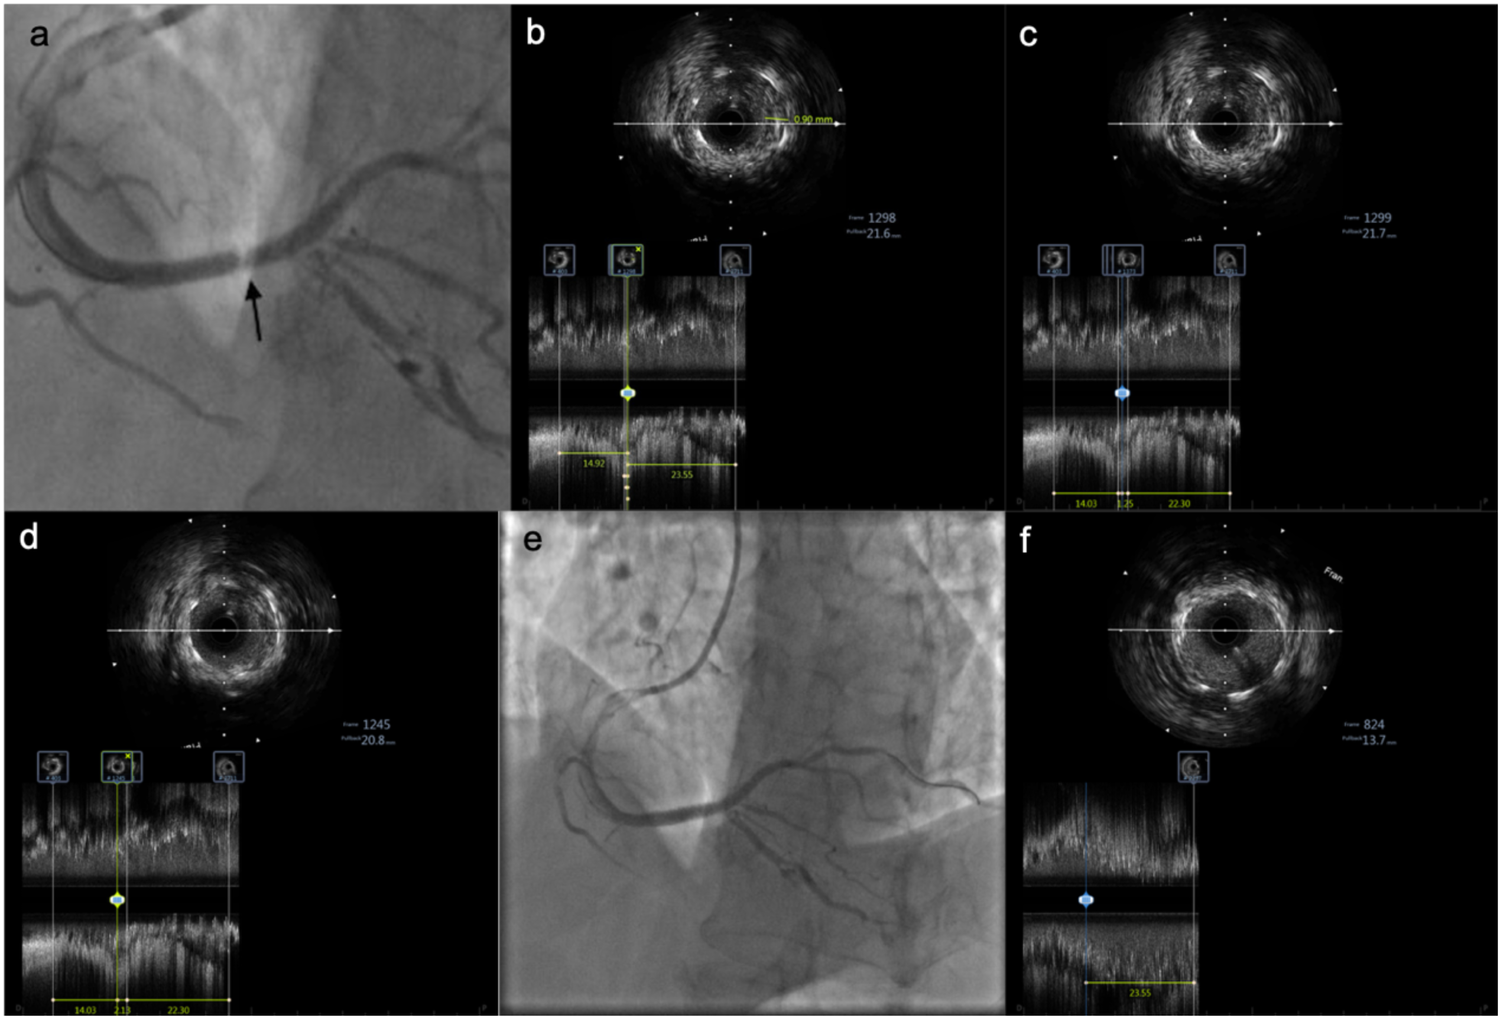

Figure 2

IVUS images showing tissue prolapse within the stent. (a) Pale appearance within the stent. (b) IVUS examination reveals tissue prolapse with a thickness of 0.9 mm. (c) Irregular tissue prolapse with an estimated area of approximately 2.01 mm2. (d) Length of the prolapsed tissue is approximately 2.13 mm. (e) Angiographic image after implantation of an additional stent at the site of prolapse. (f) At the same proximal stent location, mild tissue prolapse is observed at the 12 o'clock position, significantly improved compared to before.

for further clarification and revealed: Tissue prolapse in the mid-portion of the stent, with:

Thickness: 0.9 mm,

Length: 2.13 mm,

Area: \∼2.01 mm2 (Figure 2).

No edge dissection; good stent expansion and apposition; no stent fracture.

Repeat angiography revealed focal “hazy” appearance in mid-stent, consistent with tissue prolapse. Further balloon dilation with NC Senor 3.0 × 15 mm (14 atm, 30 s) partially improved haziness. Repeat IVUS confirmed persistent tissue prolapse.

IVUS showed significantly reduced prolapsed tissue area, no edge dissection, and well-expanded stent.

Reviewing angiographic images after the first PCI, a pale appearance was noted at the original lesion site within the stent. Subsequent IVUS imaging revealed tissue prolapse in this region, with a maximum area of 2.01 mm2 and length of 2.13 mm. An initial strategy of repeat balloon dilation was chosen, but 5 min after dilation, the pale appearance worsened on angiography, and IVUS still showed no improvement in the prolapse. The ACT remained at 290 s, confirming continued adequate anticoagulation. This strongly suggested that AST was related to the tissue prolapse.